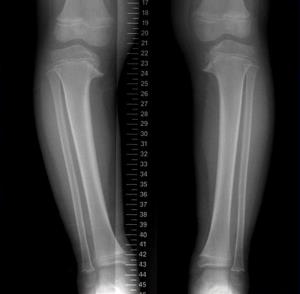

Чтобы определить это заболевание собирается общая клиническая картина. Точно наличие патологии подтверждает рентген. Если есть осложнения, проводят МРТ или КТ.

Болезнь Блаунта (синонимы: tibia vara, синдром Блаунта, синдром Блаунта-Эрлахера-Биезиня-Барбера, болезнь Эрлахера-Блаунта, синдром Мау-Нильсона) — варусная деформация (иногда вальгусная) проксимального отдела большеберцовой кости и внутренняя торсия голени, возникающая вследствие нарушения функционирования медиальной